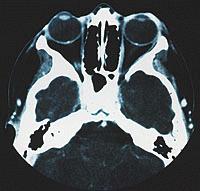

| Drusen im Sehnervenkopf/ Papille (kleine weiße Punkte) | Papille durch das Auge gesehen mit Drusen | normale Papille ohne Drusen | Querschnitt des Auges |

Unter Drusenpapille versteht man kalkartige Ablagerungen im Sehnervernkopf / Papille. Dies ist dort, wo der Sehnerv in den Augapfel gelangt. Diese Drusen können vererbt von Geburt an in der Tiefe vorhanden sein, wachsen dann erst mit dem Alter heraus. Drusen können sich aber auch bilden und vermehren. Da sie auf den Sehnerven drücken, können sie diesen schädigen. Auch die Durchblutung des Sehnerven und der Netzhaut kann erheblich gestört werden. So können die Drusen zu einer erheblichen Einengung des Gesichtsfeldes führen. Auch im zentralen Sehbereich können Drusen anscheinend verschwommenes Sehen und Flimmern auslösen, was dann zu Beschwerden wie Kopfschmerzen führt.